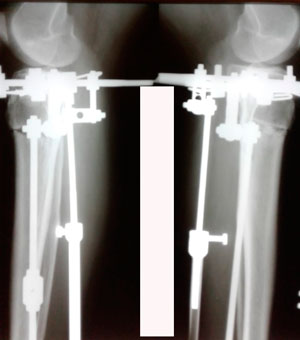

Рентген в 60 дней

IMG_7808-19-12-19-11-19.JPG

IMG_7807-19-12-19-11-19.JPG